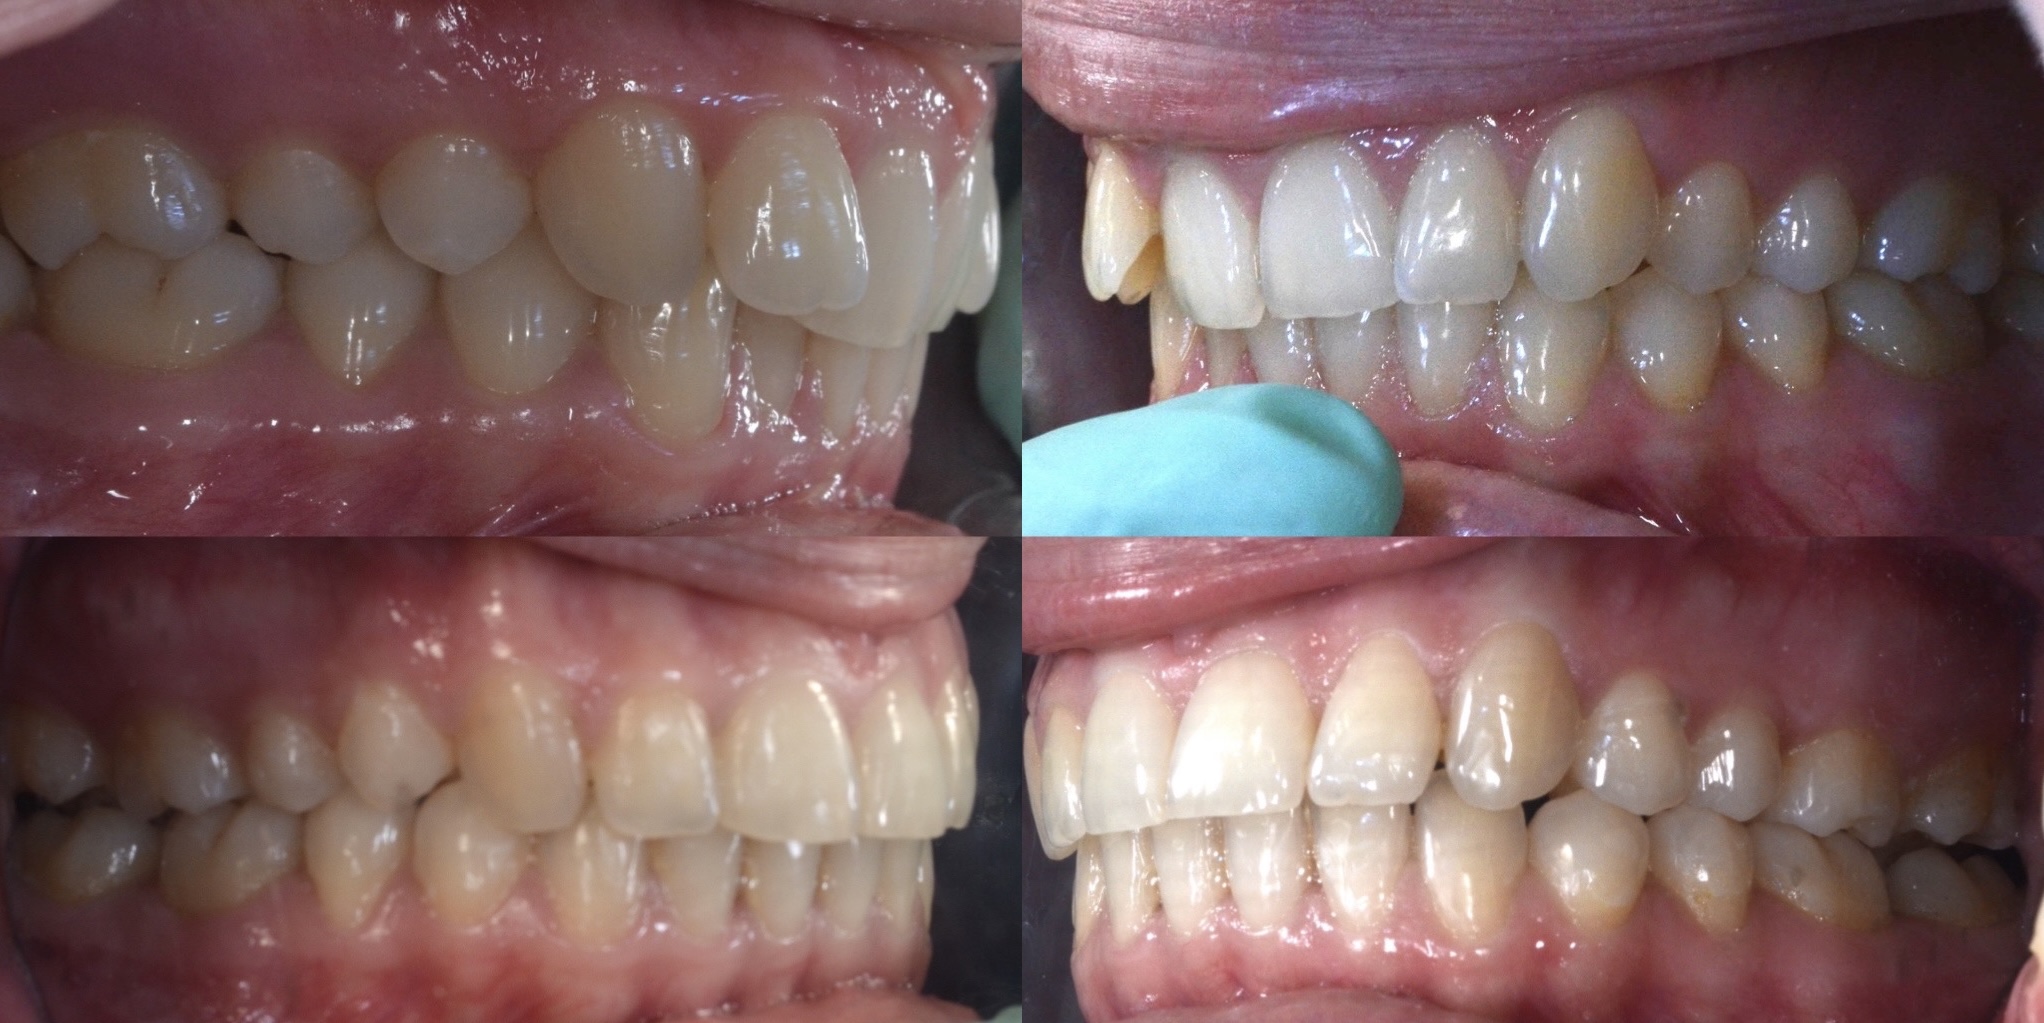

Slučaj 1: ispravljanje otvorenog zagriza i kompresije Invisalign full terapijom

Slučaj 2: ispravljanje kompresije Invisalign full terapijom- u ovom slučaju je izvađen jedan donji sjekutić

Slučaj 3: ispravljanje kompresije Invisalign full terapijom

Slučaj 4: ispravljanje kompresije Invisalign full terapijom

Slučaj 5: ispravljanje kompresije i križnog zagriza Invisalign full terapijom

Slučaj 6: ispravljanje kompresije i dubokog zagriza Invisalign full terapijom

Slučaj 7: ortodontska predprotetska terapija Invisalign full